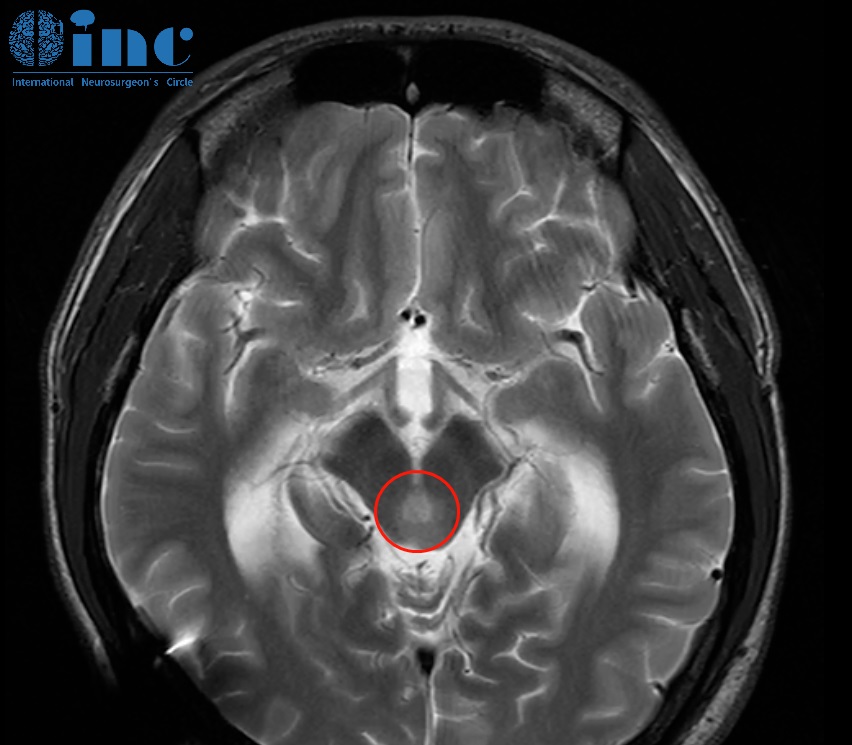

2021年2月张远不幸MRI检查出中脑顶盖占位性病变,疑似胶质瘤,较大直径约8mm,2022年8月张远病情再次加重,复查磁共振提示肿瘤增大,此时肿瘤较大直径12mm,2022年10月复查核磁提示肿瘤增大,自行测量肿瘤大小约18mm,两月内竟激增6mm!肿瘤越来越大,然而四处寻医的结果却是脑干位置风险太大,无法手术。但是家人并没有放弃,然后在2022年巴教授示范手术期间,巴教授顺利为张远近全切肿瘤。在巴教授顺利为张远进行近全切手术后,术后半年随访中,张远恢复良好,行动自如。巴教授查看了他的复查影像后回复道:

“附件随访检查的相关MRI切片。它们记录了中脑好的方面,没有肿瘤残留或复发。所以手术和术后放化疗似乎合适!

我很惊讶这个肿瘤是一个多形性黄色星形细胞瘤,因为这些肿瘤很少在那个部位出现,但这个诊断比高度胶质瘤好得多。我认为目前病人不需要任何不同的额外治疗,只需要观察。

目前看来,6个月后患者可能不需要长期化疗,我们将观察未来反复MRI对照的情况。”

术后一个多月,张远病理结果为2级多形性黄色星形细胞瘤,多形性黄色星形细胞瘤是预后相对较好的星形细胞瘤,巴教授对于后续的治疗也给出了相应建议,可进行后续的放化疗。术后半年再完成了相关后续治疗后,巴教授随访中也对后续治疗效果表示了肯定“手术和术后放化疗似乎合适!”“后续不再需要任何不同治疗”。20出头的他终于能够安心于学业,继续书写未来的人生画卷。